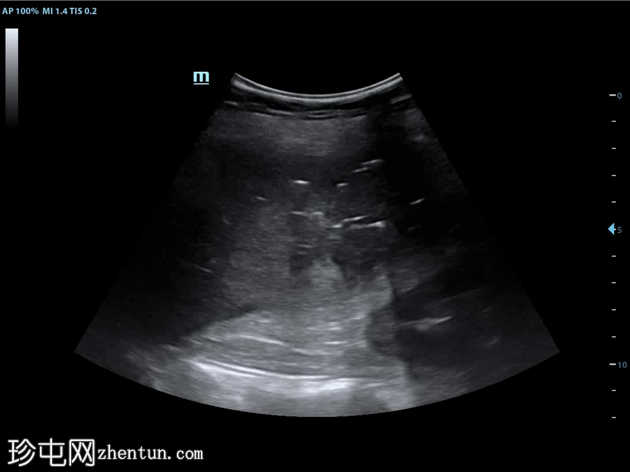

CT

轴位

非增强

肝段 6 和 7 可见多房性积液,呈环状强化

积液内可见多个气体腔

破入肝包膜下间隙,可见肝包膜下积液及气体腔

壁层腹膜与前腹壁之间可见另一局灶性积液

肝段 7 的肝内胆管局灶性扩张(0.3cm),内含气体腔

其他肝内胆管和肝外胆管均正常

胆囊缺失,可能由于既往胆囊切除术所致

无游离液体。

双侧肾皮质囊肿

轻度右侧胸腔积液伴邻近肺不张

超声表现符合气肿性肝脓肿。数小时后进行的肝脏增强 CT 多期扫描显示气肿性肝脓肿破裂。